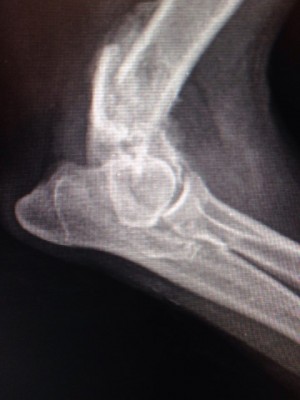

Надо мелкой рентген срочно делать

На лапу не наступает.... гипс не помню сколько был, но возможно, не правильно сложили

Вобщем все гораздо хуже оказалось.Только характер приятный,ласкавая.

Очень паршивый перелом.... сложная операция.

Не понятно куда и зачем одевали гипс.... зато стерилизовали.